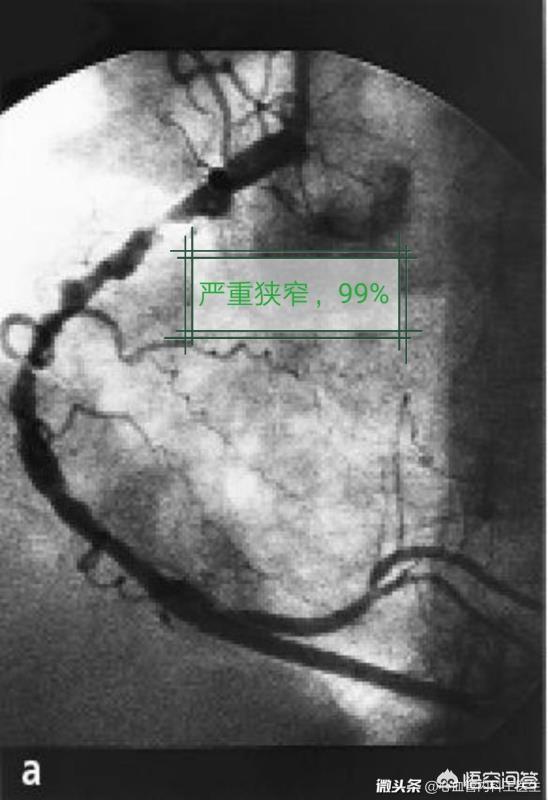

1) Les patients présentant une sténose légère des artères coronaires, une sténose ayant peu d'effet sur la circulation sanguine ou des lésions vasculaires mineures de moindre importance sont généralement traités uniquement avec des médicaments et font l'objet d'un suivi régulier pour observation. Si un stent est implanté à ce moment-là, il risque de faire plus de mal que de bien.

1, stent vide (stent métallique nu) : le stent est un corps étranger au corps humain, qui l'"attaque", provoque une hyperplasie des cellules endothéliales et une réaction inflammatoire, ce qui peut entraîner une re-sténose et une obstruction des vaisseaux sanguins lisses. L'incidence de la resténose et de l'obstruction des endoprothèses vierges atteint 30 %, et ces endoprothèses ne sont plus utilisées.

2、Drug stent : Afin d'éviter une nouvelle obstruction après la pose d'un stent cardiaque, un film de médicament est enduit à la surface du stent métallique, ce qui constitue un stent médicamenteux. Après l'implantation de ce type de stent dans le corps, le médicament est libéré lentement pour inhiber la croissance du tissu cicatriciel autour du stent et maintenir l'artère coronaire ouverte. L'incidence de la resténose et de l'obstruction de l'artère coronaire est ainsi réduite à 10 %.